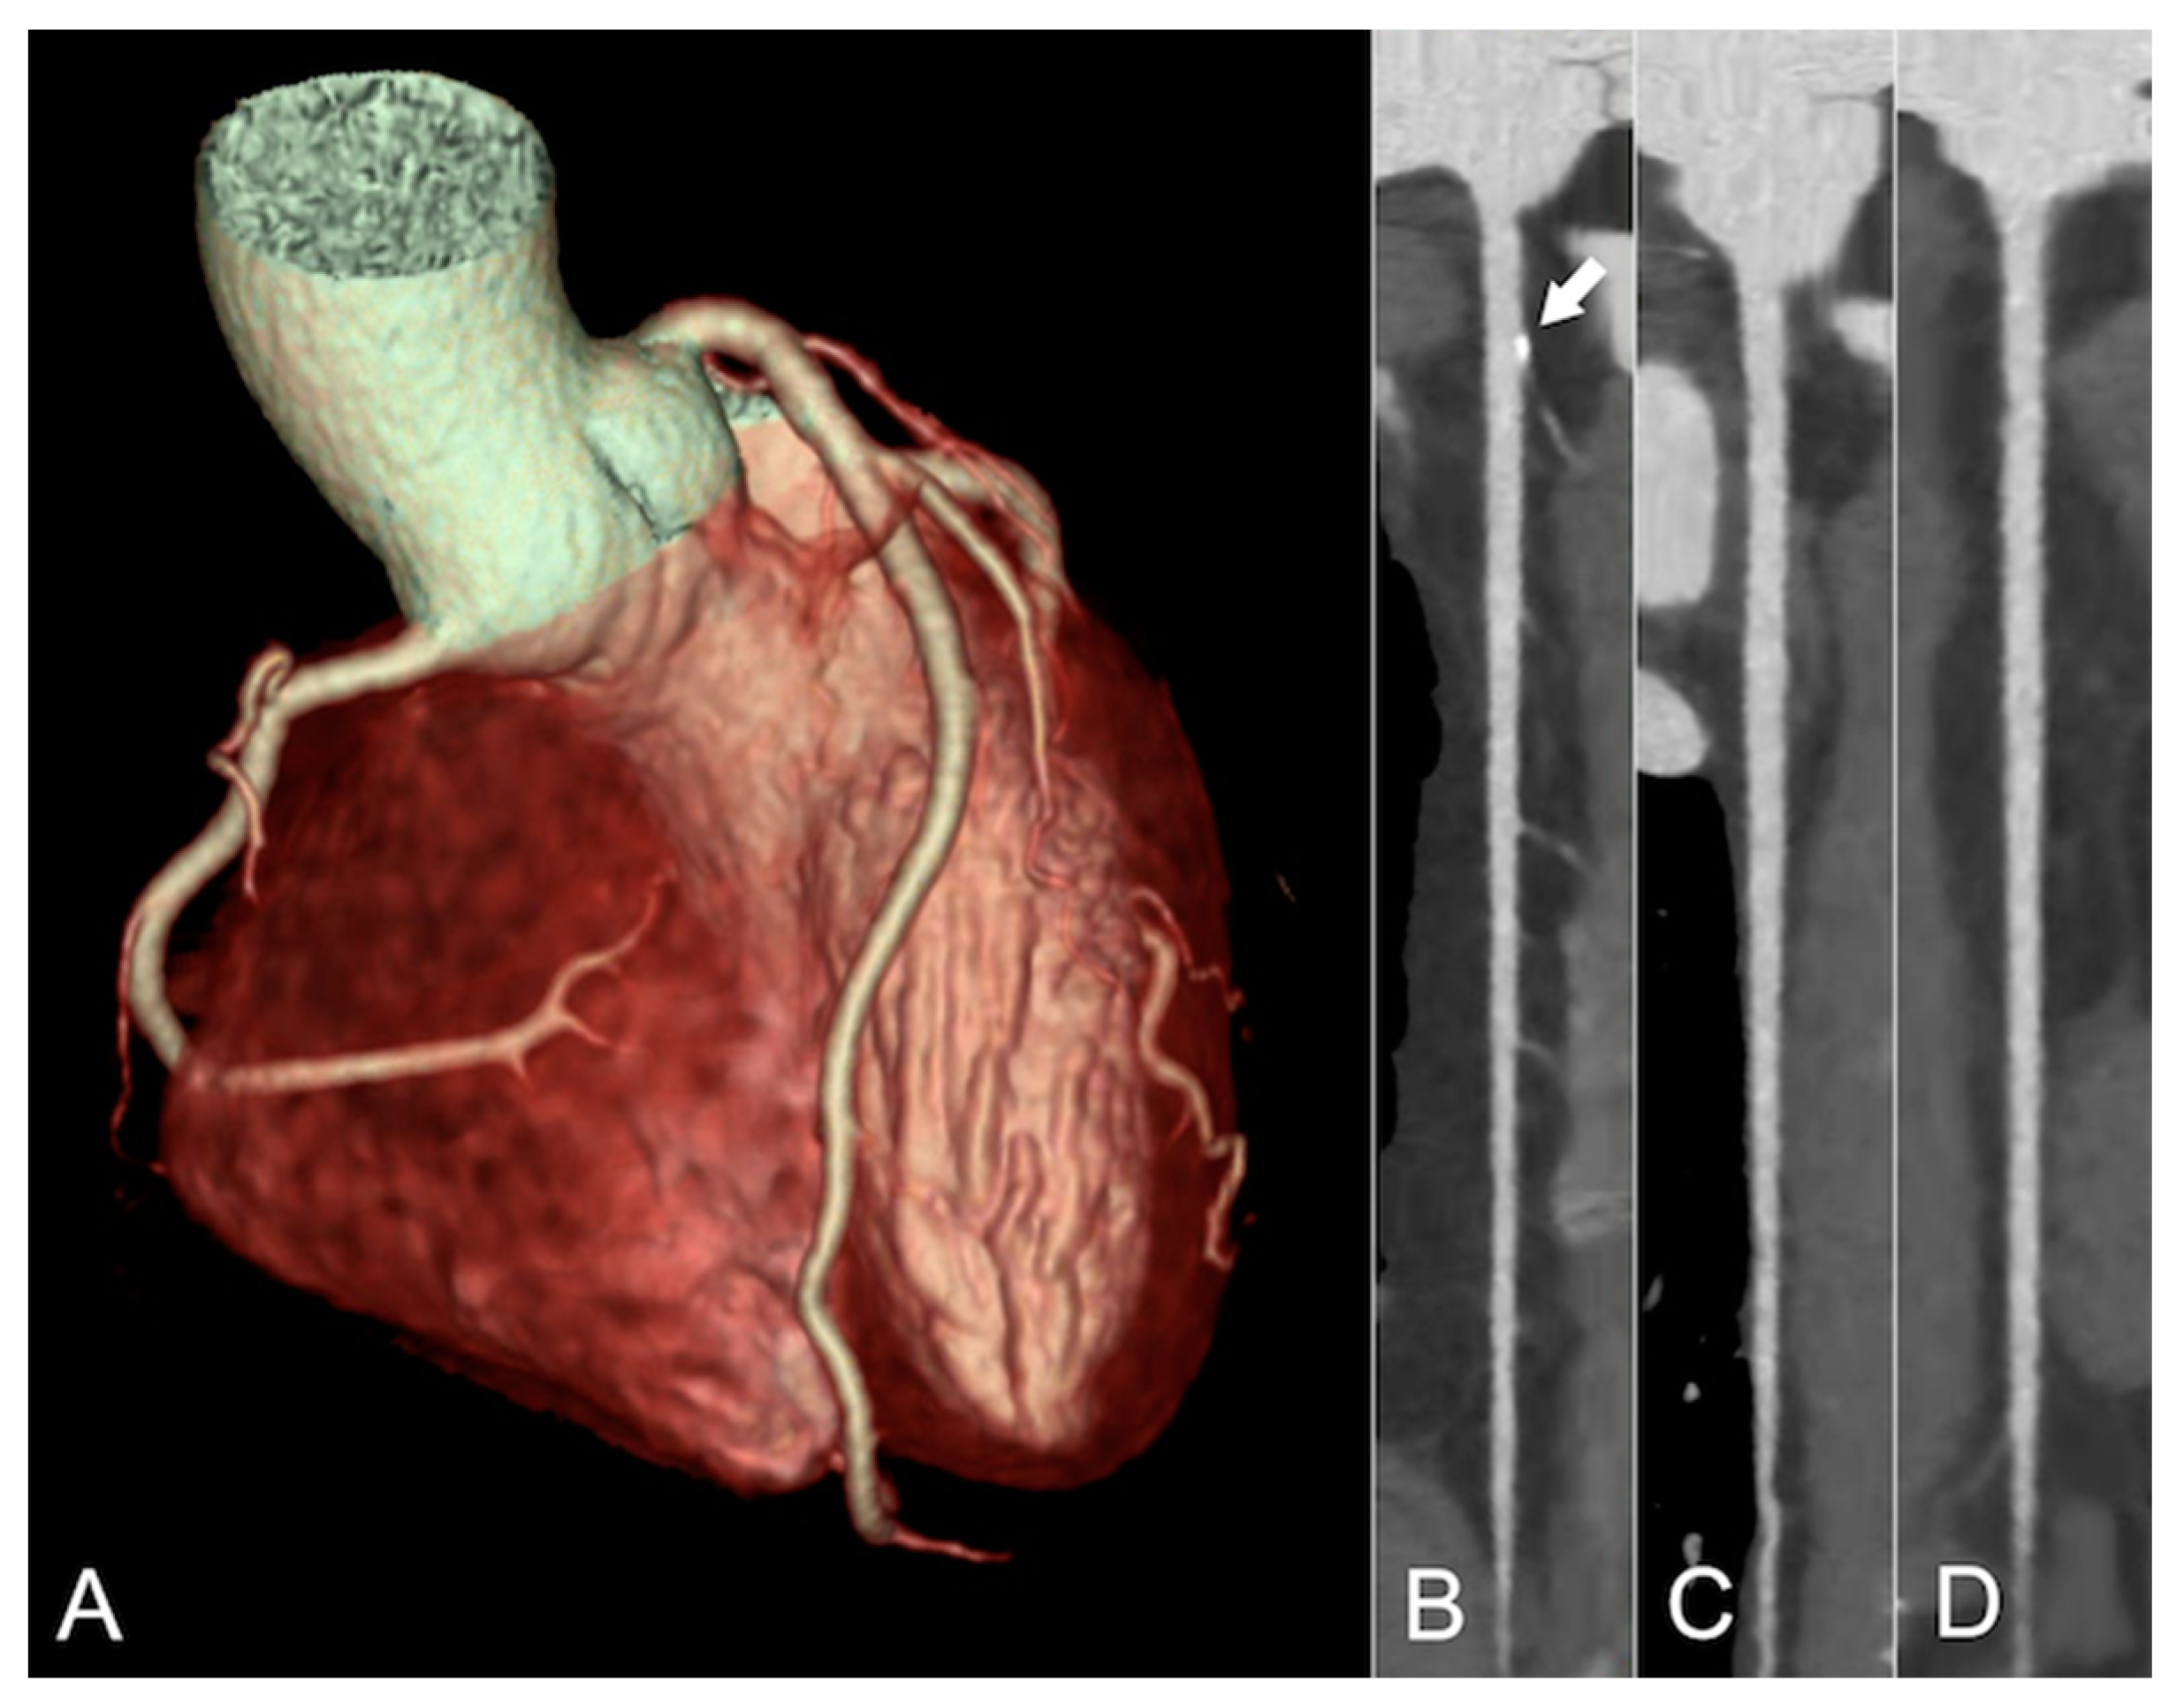

3. Coronary Artery Calcium (CAC) Scoring

4. Coronary CT Angiography (CCTA)